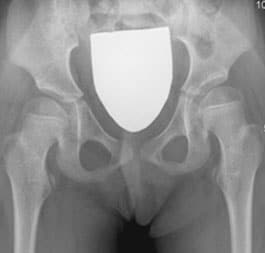

One of the surgical procedure, originally described by Professor Portinaro and his team, to maintain or restore the correct relationships between the femur and the acetabulum, is called temporary medial hemiepiphysiodesis of the proximal femur (TMH-PF). Epiphysiodesis is a surgical procedure that aims to stop or slow the growth of a cartilage.

The surgical technique consists of inserting a cannulated screw into the femoral neck to prevent the femoral head from progressively move out of its natural socket.